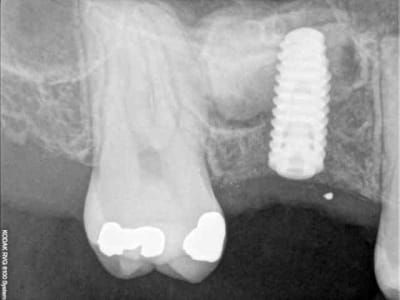

je sais pas si c'est un produit miracle, mais pour les sinus lift, c'est fantastique.

outre le fait de stabiliser un implant dans un sinus type SA4, pas de risque de voir partir le produit comme avec les granules de bioos et autres..

l'autre avantage est de ne pas avoir à mettre de membrane de recouvrement.

je suis donc hyper satisfait du résultat.

jugez plutôt...

quasiment 6 mois entre les deux interventions (sinus lift et mise à jour)

c'est surtout la qualité des trabéculations osseuses qui m'interpelle.

d'habitude, on voit toujours un peu de particules, ici, c'est vraiment top.

je crois que c'est la première fois que je vois une cliché radio à quelques mois post-op avec ce matériau et le résultat semble excellent.